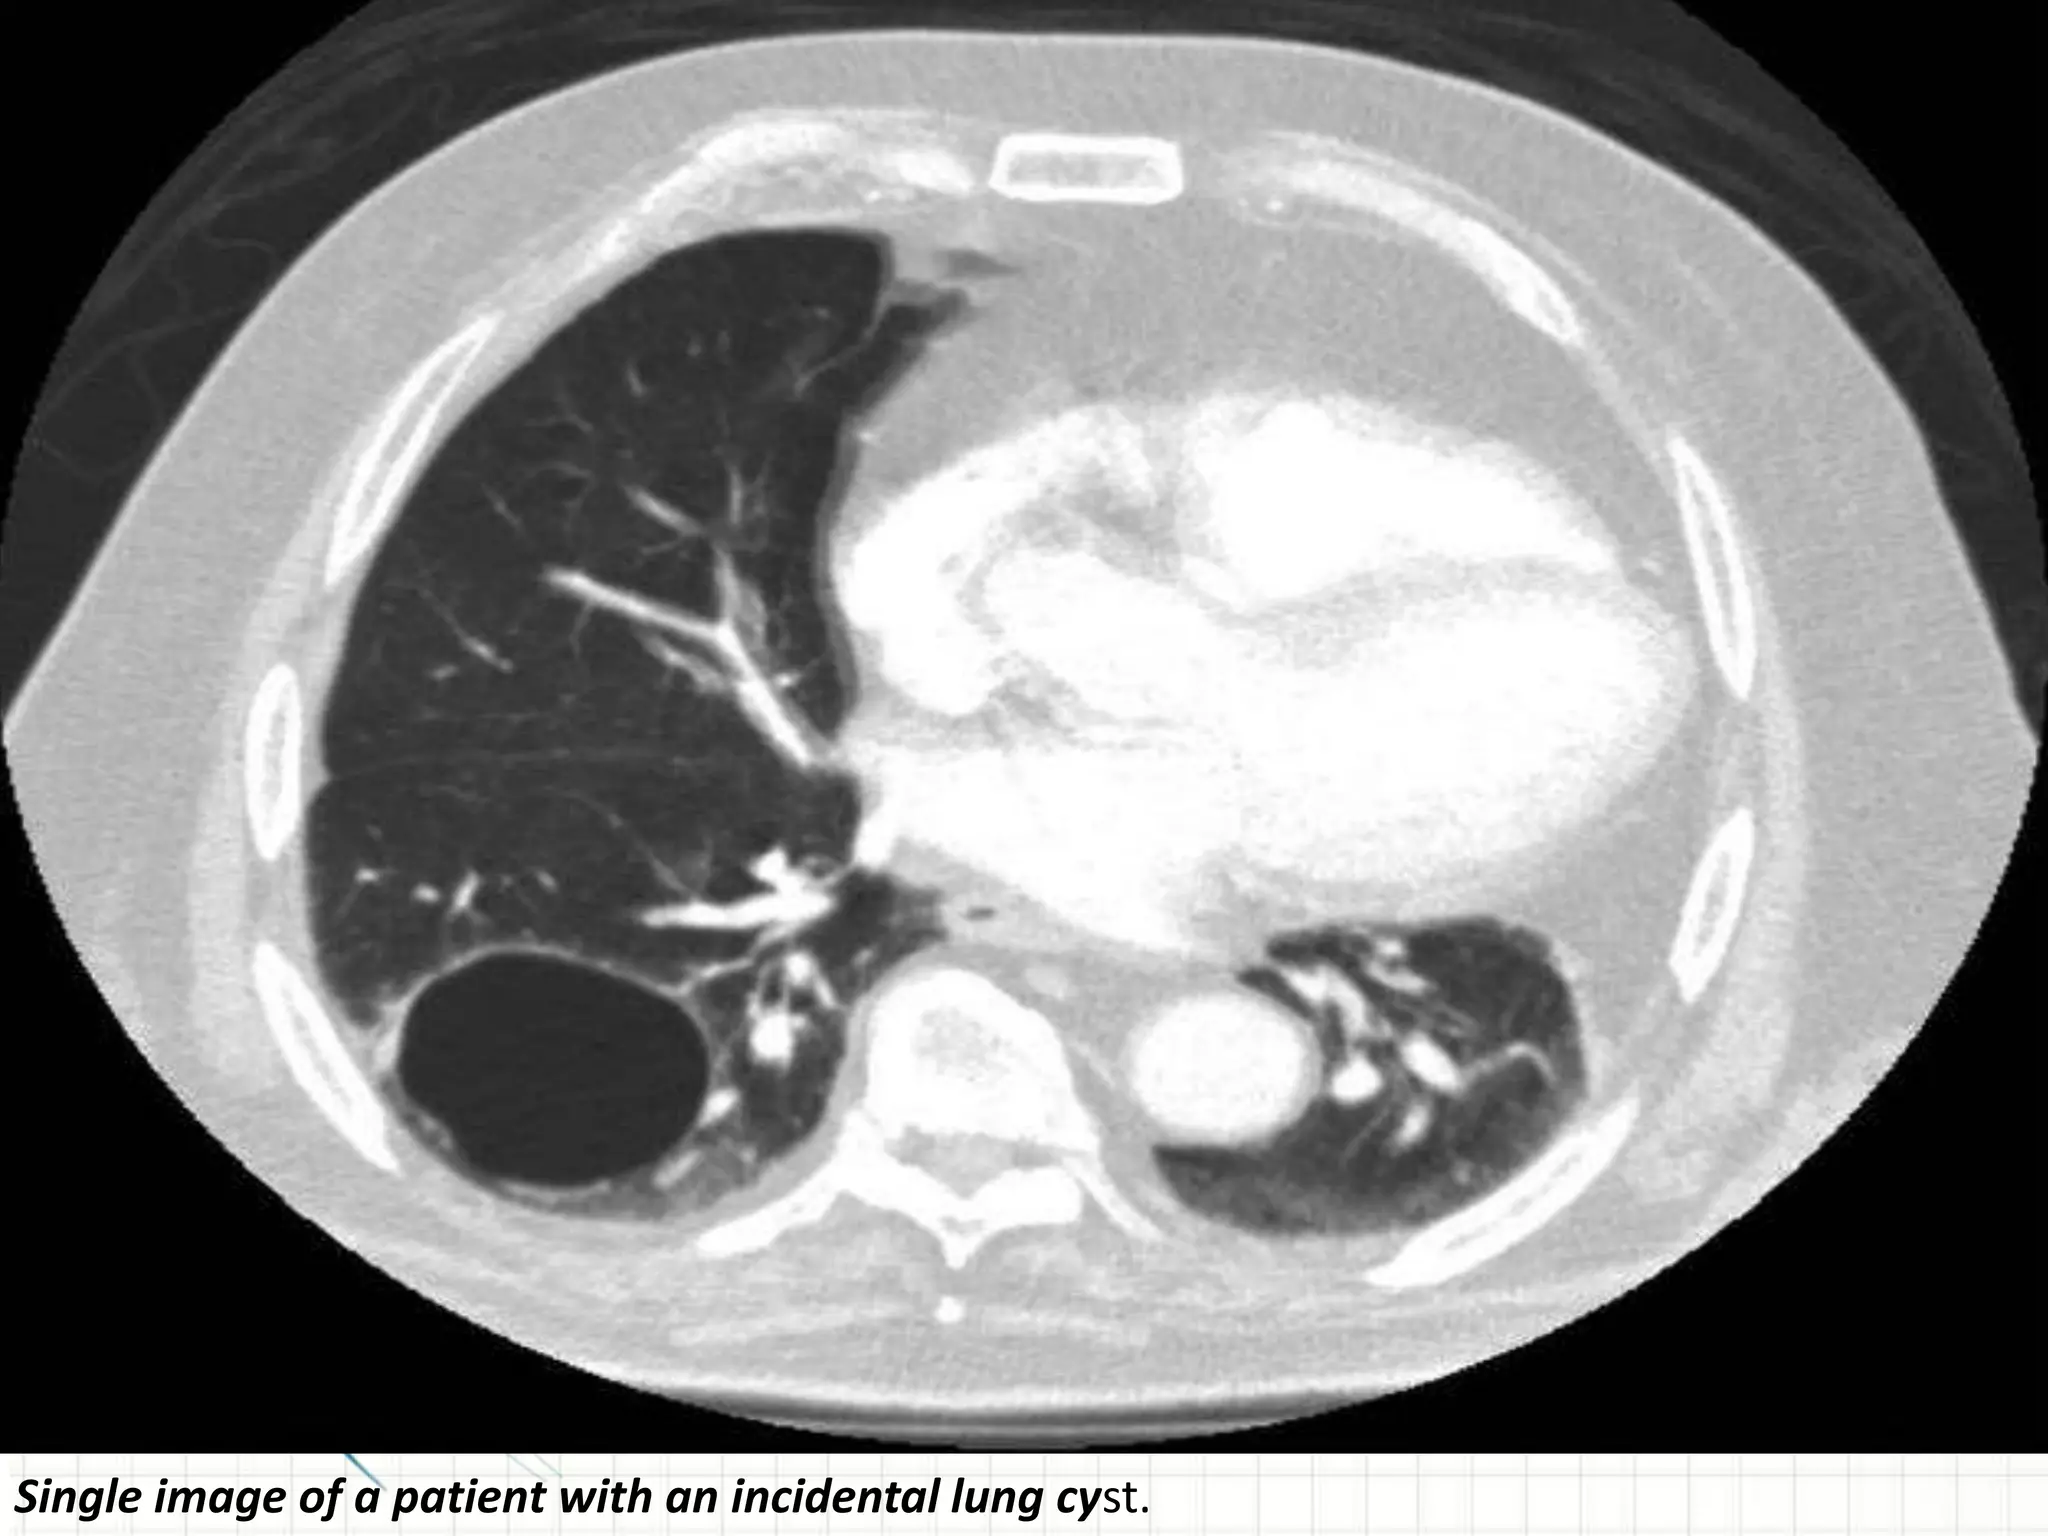

Single image of a patient with an incidental lung cyst.

Single image ofa patient with an incidental lung cyst.